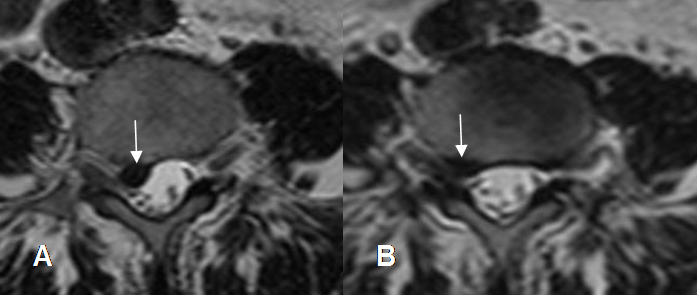

Fig 109. Regresión de hernia.

A y B: RM axial en T2. Hernia paramediana derecha. En un control posterior, ha disminuido el tamaño y la compresión de las raíces.